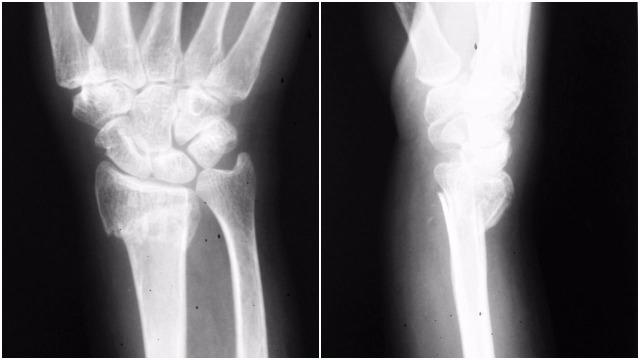

Although it is common for separate elbow joint dislocation and fracture of forearm bones to occur, it is a rare sighting for both elbow dislocation and ipsilateral fracture of the distal radius. We report a case of an anterior dislocation of the elbow with ipsilateral fracture of the distal radius. The case was treated operatively. We describe two possible mechanisms of injury for these rare injury types. The case underlines the importance of assessing the wrist in the case of an elbow fracture and vice versa.

虽然肘关节脱位和前臂骨骨折单独发生很常见,但肘关节脱位和同侧桡骨远端骨折同时出现则较为罕见。我们报告一例肘关节前脱位合并同侧桡骨远端骨折的病例。该病例接受了手术治疗。我们描述了这些罕见损伤类型的两种可能损伤机制。该病例强调了在肘关节骨折时评估腕关节以及在腕关节骨折时评估肘关节的重要性。